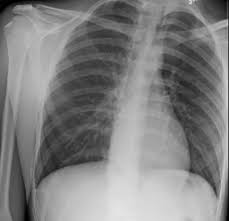

Patients with a pneumothorax typically report dyspnoea and chest pain. It is not intended to provide medical advice on personal health matters or to guide treatment — which is only appropriately done by a qualified health professional. Delayed Spontaneous Bilateral Pneumothorax In A Previously Healthy Nonventilated Covid 19 Patient Journal Of Emergency Medicine Source: els-jbs-prod-cdn.jbs.elsevierhealth.com